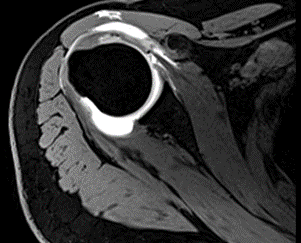

此外,该设备除常规磁共振检查外,对头颈血管壁高分辨率分析、心脏形态及功能的无创性检查也达到了相当高的水准。不仅大幅度提高病人心脏扫描的舒适性,而且保证极高心脏成像质量。